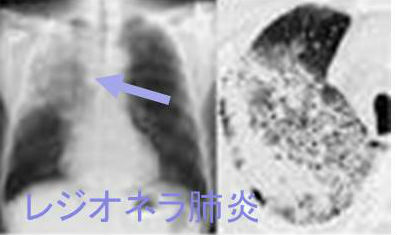

レジオネラ肺炎とは

レジオネラ菌は水場を好むため、エアコン・加湿器(特に家庭用超音波式加湿器)・うがいの行列ができる水場・循環式風呂/温泉、貯めていた雨水が感染源になります。実際、スーパー銭湯や大浴場で集団感染(アウトブレイク)が起こり、死亡者が出た事件もありました。また、井戸水を使用したり、貯めていた雨水で庭に水をまいたりして感染する例もあります。

レジオネラ肺炎は届出義務のある4類感染症です。非定型肺炎ですが、免疫抑制剤・副腎皮質ステロイド剤投与中の関節リウマチや糖尿病の免疫不全患者で劇症肺炎化(大葉性肺炎)し、横紋筋融解症も引きおこします[(甲状腺機能亢進症/バセドウ病,甲状腺機能低下症/橋本病の様)]。[Clin Case Rep. 2024 Mar 7;12(3):e8628.][Respir Med Case Rep. 2020 Dec 9;32:101321.]

レジオネラ肺炎では、

- SIADH(抗利尿ホルモン不適合分泌症候群)による低ナトリウム(Na)血症(約46%)[BMC Infect Dis. 2013 Dec 11:13:585.]

- 低リン血症;近位尿細管障害の可能性

- 中枢神経症状;頭痛、意識障害からけいれん(甲状腺クリーゼ/粘液水腫性昏睡の様)、(甲状腺機能亢進症/バセドウ病の様)

も起こります。

喀痰グラム染色で多核好中球を多数認めても、明らかな原因菌は確認できません(レジオネラは細胞内寄生菌のため)。

以前はレジオネラ菌の培養同定に数日を要し、その間にレジオネラ肺炎が悪化していましたが、現在は尿中レジオネラ抗原検査が可能になり、3時間で迅速に診断できます。ただし、尿中レジオネラ抗原検査キットは70%しか陽性になりません。

レジオネラ肺炎の胸部CTは特徴的な「広範に広がるすりガラス陰影内に,区域性/亜区域性の気管支血管束周囲の斑状浸潤陰影」。実際の写真を見た方が解り易いです。

レジオネラは細胞内寄生細菌で、宿主細胞に浸透する

- ニューキノロン系;ニューキノロン剤の静脈投与が第一選択

- マクロライド系(エリスロマイシンなど)+リファンピシン

の抗生剤を使用。リファンピシンは薬剤性甲状腺機能低下症の原因になります。

セフェム系、カルバペネム系抗生剤は細胞内移行が悪く、ほとんど無効。